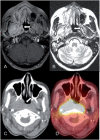

Amyloidosis comprises a rare spectrum of protein deposition diseases that diffusely or focally affect any organ. Amyloid's variable clinical presentation and nonspecific disease course often cause it to evade early diagnosis. This pictorial essay aims to familiarize radiologists with the pathophysiology of amyloidosis, to describe the basic classifications of amyloidosis, and to use multimodality imaging to illustrate its varied appearance throughout the body. This review highlights the diagnostic challenge of interpreting radiographic studies in patients with hematologic malignancies and concurrent amyloidosis. Radiologists should consider amyloid in chronically ill patients or patients with hematologic malignancies who have unusual/unexpected imaging findings.